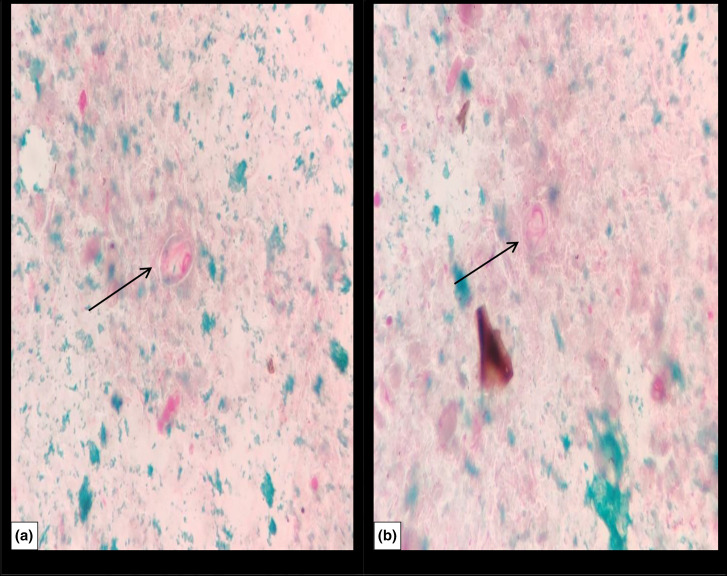

贾第虫病是由原生动物肠道贾第虫引起的小肠感染,是世界上最常见的人类肠道寄生虫病之一。它主要表现为免疫功能正常的患者的自限性疾病,通常不需要治疗。然而,免疫缺陷是严重贾第鞭毛虫感染发病的一个危险因素。本文报告一例复发性贾第虫病对硝基咪唑治疗无效。一名7岁男性类固醇抵抗性肾病综合征患者因慢性腹泻来我院就诊。患者长期接受免疫抑制治疗。粪便显微镜检查显示大量滋养体和肠芽孢囊。在本病例中,甲硝唑治疗时间比推荐时间长,未能清除寄生虫。

Giardiasis is an infection of the small intestine caused by the protozoan parasite Giardia intestinalis and one of the most common parasitic intestinal diseases in humans worldwide. It mainly manifests as a self-limited illness in the case of immunocompetent patients and usually does not require treatment. However, immunodeficiency is a risk factor for the onset of severe Giardia infection. In this report, a case of recurrent giardiasis refractory to nitroimidazole therapy is presented. A 7-year-old male patient with steroid-resistant nephrotic syndrome came to our hospital because of chronic diarrhoea. The patient was on long-term immunosuppressive therapy. Microscopic examination of stool showed a significant number of trophozoites and cysts of G. intestinalis. Treatment with metronidazole for longer duration than recommended has failed to clear the parasite in the present case.